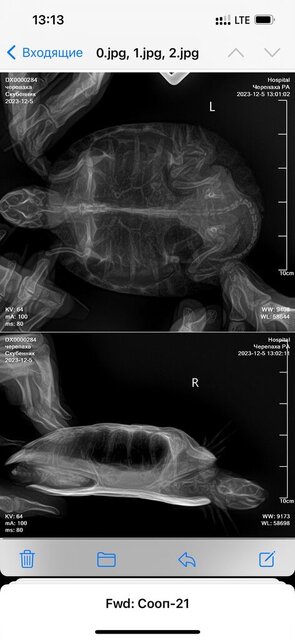

Консультанты moth Ваше имя: Мария Локация: Москва Опубликовано: 2 декабря 2023 Консультанты Опубликовано: 2 декабря 2023 @Инна Марченко активность выше тоже не стала? Вы рентген ей сможете сделать?

Инна Марченко Ваше имя: Инна Локация: Россия, г.Находка Опубликовано: 3 декабря 2023 Автор Опубликовано: 3 декабря 2023 Да, хорошо, записалась в клинику на рентген, правда прием только через 2 дня Пока что продолжаю лечение только каплями?

Консультанты moth Ваше имя: Мария Локация: Москва Опубликовано: 3 декабря 2023 Консультанты Опубликовано: 3 декабря 2023 @Инна Марченко пока да, только капли проекции желательно сделать все три, но хотя бы две - под номерами 1 и 3, чтобы было видно и лёгкие и желудок

Инна Марченко Ваше имя: Инна Локация: Россия, г.Находка Опубликовано: 5 декабря 2023 Автор Опубликовано: 5 декабря 2023 Здравствуйте, вот сделали рентген

Консультанты moth Ваше имя: Мария Локация: Москва Опубликовано: 5 декабря 2023 Консультанты Опубликовано: 5 декабря 2023 @Инна Марченко я отправила снимки нашему врачу, напишу как она ответит сейчас что-то в поведении изменилось в лучшую/худшую сторону?

Инна Марченко Ваше имя: Инна Локация: Россия, г.Находка Опубликовано: 5 декабря 2023 Автор Опубликовано: 5 декабря 2023 Все так же, глазки открываются немного, но не до конца и снова закрываются, уже 9 дней прокапала, кушать все так же отказывается

Консультанты moth Ваше имя: Мария Локация: Москва Опубликовано: 6 декабря 2023 Консультанты Опубликовано: 6 декабря 2023 @Инна Марченко это просто болячка была и отвалилась. Наш врач ответила, что у черепахи признаки вторичного пищевого гиперпаратиреоза. Кровь на анализ не получится взять? Тут нужны уколы кальция. Купите глюконат кальция в ампулах (чел) или борглюконат кальция (вет), 5 инсулиновых шприцев. Я ещё уточню можно ли делать укол витаминов, т.к. не понятно что именно кололи вашей. Вообще никак не узнать названия препаратов?